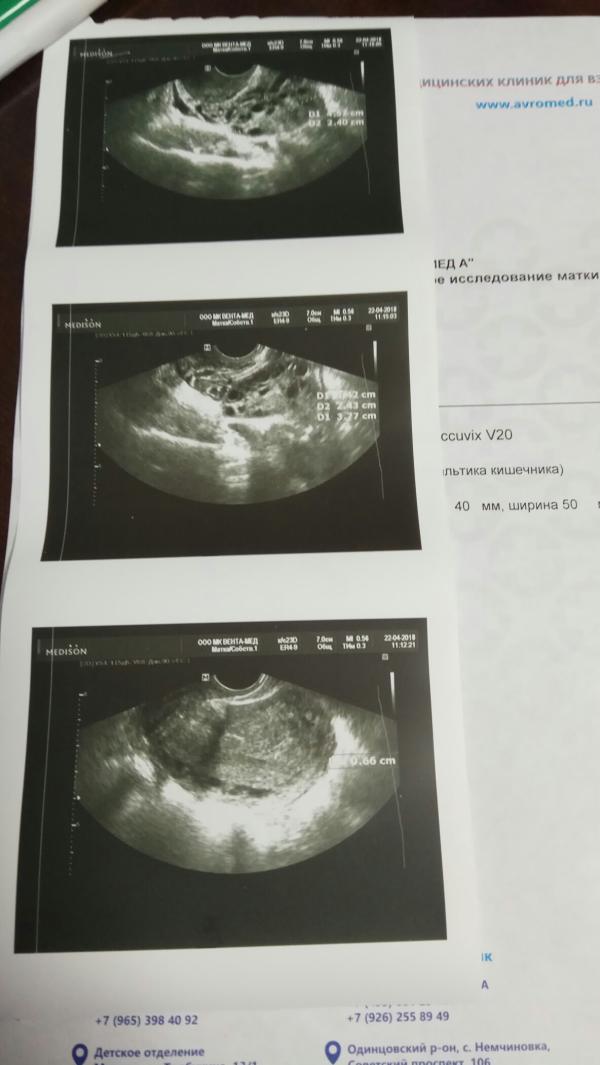

@novi83 так все написано же. Кист полно на яичниках. По более 15 шт. Жидкость до 5мл за маткой.

Вообще странно, что яичники не описаны.

Не написано что в полости живота за маткой есть или нет жидкость и т.д.

УЗИ явно не очень получилось.

Надо бы ещё раз сделать.

Т.к. если не видно в каком состоянии яичники из размеры, фоликулярную активность. Нет ли там кист или жёлтых тел...

То очень сложно сказать, что с организмом....